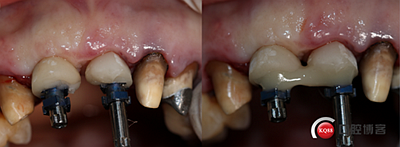

鄰牙重新備牙,制作臨時樹脂橋體,缺牙區(qū)三顆變?yōu)閮深w。下圖是術(shù)后一個月口內(nèi)照。

術(shù)后兩個月。

術(shù)后4個月,三顆牙變?yōu)閮深w牙齦乳頭改造是難點。